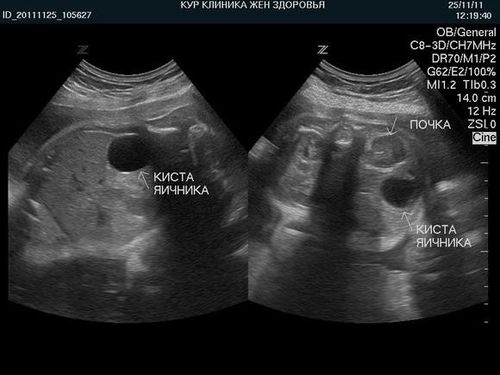

Эксперты в области ультразвуковой диагностики отмечают, что различие между кистой и беременностью на УЗИ может быть не всегда очевидным, особенно на ранних сроках. Кисты яичников, как правило, представляют собой заполненные жидкостью образования, которые могут иметь схожие характеристики с зародышем. Однако опытные специалисты способны различать эти состояния благодаря специфическим признакам. Например, наличие сердцебиения и эмбриональных структур указывает на беременность, тогда как киста не будет демонстрировать таких признаков. Тем не менее, в редких случаях, особенно при наличии сложных кист, может возникнуть путаница. Поэтому важно проводить дополнительные исследования и консультации с врачом для точной диагностики.

Кистозное новообразование имеет вид небольшого отекшего шарика, который внешне схожий с плодным яйцом в первые недели после зачатия. Поэтому кисту яичника очень просто спутать с беременностью. Если возникли сомнения по поводу правильности постановки диагноза, то рекомендуется повторно пройти диагностику через пару недель.

Трансвагинальное УЗИ является наиболее информативным методом для диагностики заболеваний органов малого таза. Этот метод позволяет получить более четкое изображение яичников и матки, что особенно важно для выявления кист. При трансвагинальном УЗИ датчик вводится во влагалище, что обеспечивает близость к исследуемым органам и позволяет лучше визуализировать их структуру. Кисты обычно выглядят как однородные, заполненные жидкостью образования, которые могут иметь четкие или нечеткие границы.

На УЗИ киста обычно выглядит как однородное образование с четкими границами, заполненное жидкостью, тогда как беременность проявляется в виде эмбриона или плодного яйца с характерными признаками, такими как сердцебиение. Врач также может оценить уровень гормонов и другие клинические данные для более точной диагностики.